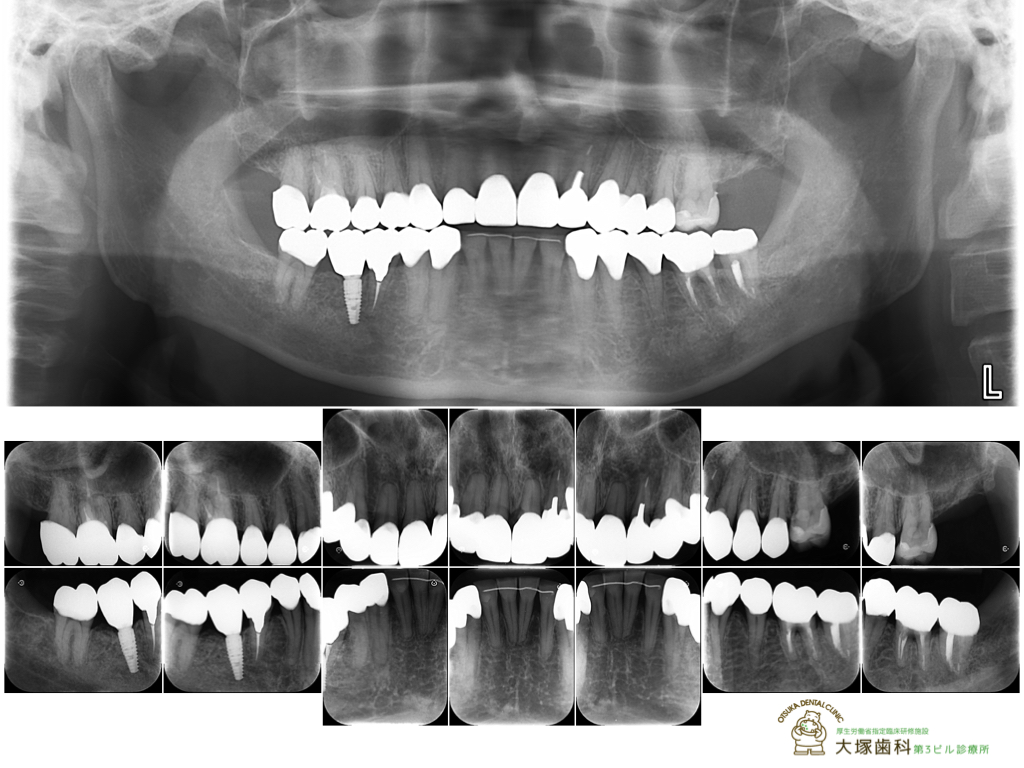

[レントゲン術後]